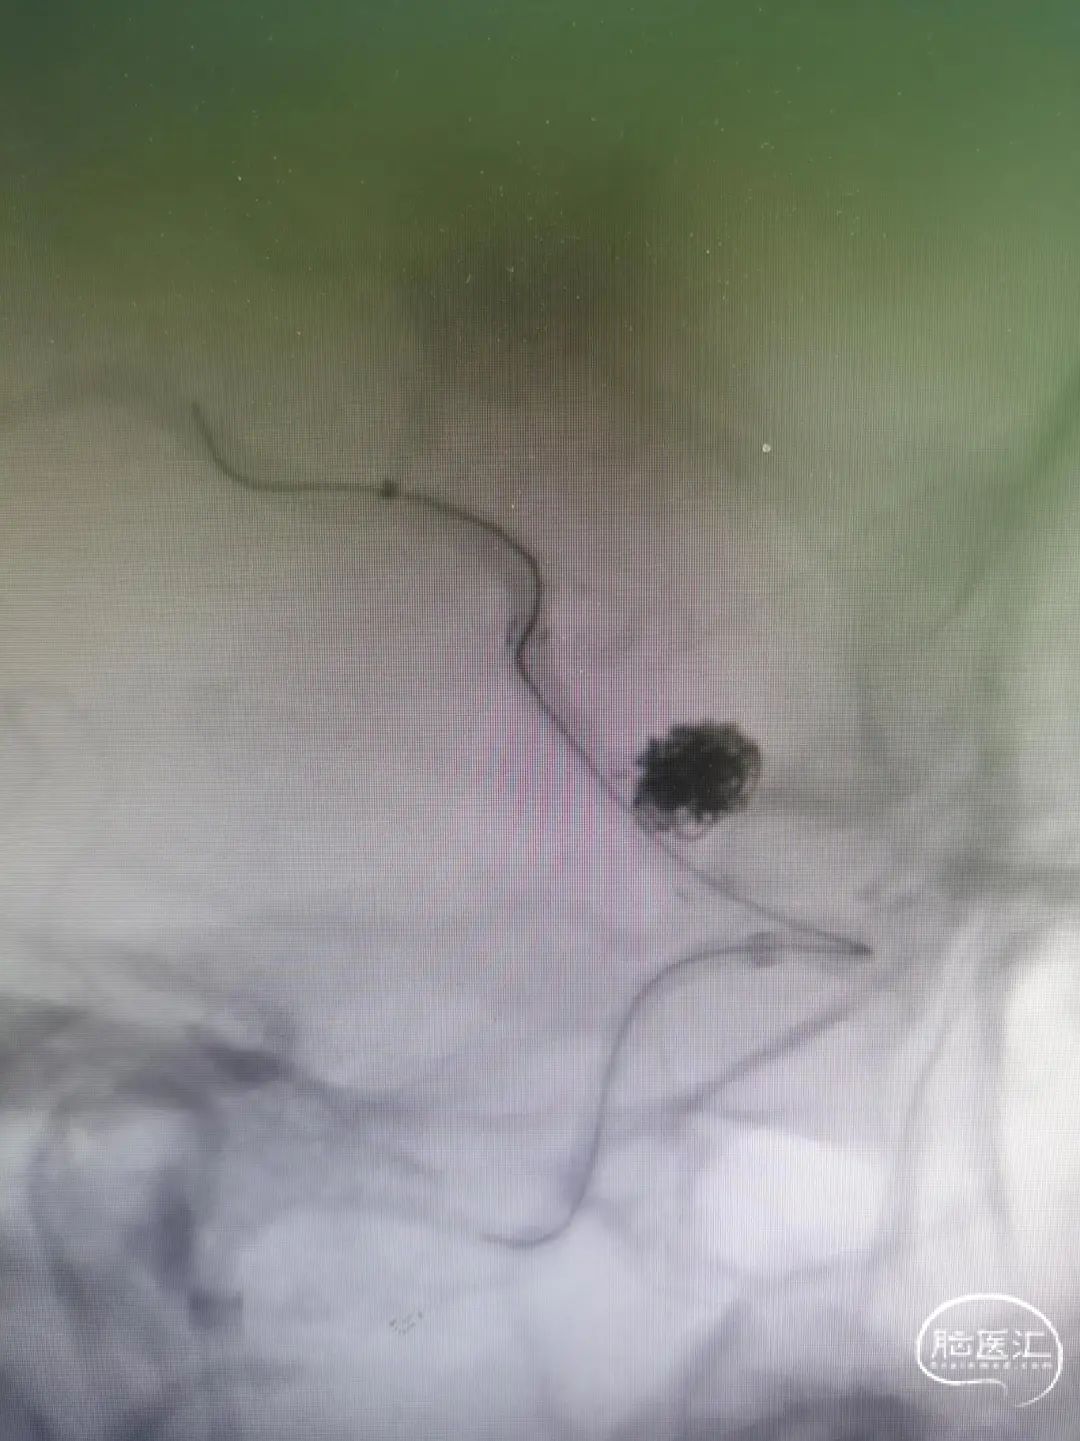

XT-17微导管穿网孔进入瘤腔;A为XT17远端Mark点,B为XT17近端Mark点。

XT-17微导管依次填入Target 5-15/4-8/2-6/2-6/1.5-3,造影确认填塞效果基本满意。

用导丝成袢带XT-27支架导管到位时卡住辅助支架近端Mark,前推XT-27增张后透视下发现辅助支架近端少了一个Mark点,疑似支架近端钢梁被XT-27推得内翻。XT-27顺利到位,预置在大脑中M2。